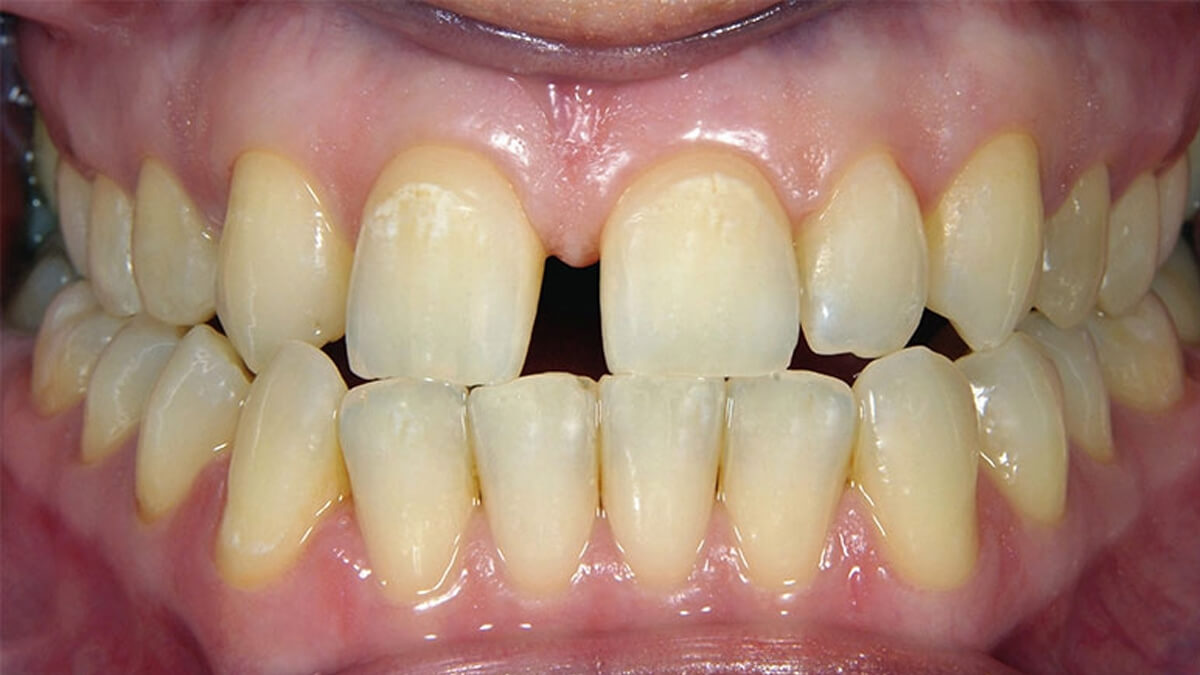

fogszuvasodás kezeléseSzájüregünkben, a fogak felszínén, az ínyen, a nyelvünkön számos baktérium található, melyek fontos szerepet játszanak a biológiai egyensúly fenntartásában. Néhány baktérium azonban a táplálkozásunk során elfogyasztott szénhidrátot képes lebontani úgy, hogy közben sav keletkezik. Ennek következménye, hogy étkezés után csökken szájüregünk pH-értéke, azaz savas közeg alakul ki, amelyet nyálunk semlegesítő hatása egy idő után helyreállít. Abban az esetben, ha gyakran fogyasztunk szénhidráttartalmú ételeket, nincs idő, hogy a savak semlegesítődjenek, ezért hosszan tartó alacsony pH-jú időszakok alakulnak ki, s elkezdődik a fogszuvasodás.

Fogaink külső felszínét szervezetünk legkeményebb anyaga, a zománc borítja. A zománc 98%-át szervetlen anyagok alkotják, amelyek savhatásra képesek kioldódni. Ez a magyarázata annak, hogy egy ilyen kemény anyag képes meggyengülni, sőt üreg képződhet pusztán baktériumok és szénhidrát hatására. Abban az esetben, ha a kórokozók átjutottak a zománc rétegen, a fogszuvasodás terjedése felgyorsulhat , ilyenkor általában már panaszos a fog, hidegre, édesre intenzívebben reagál.